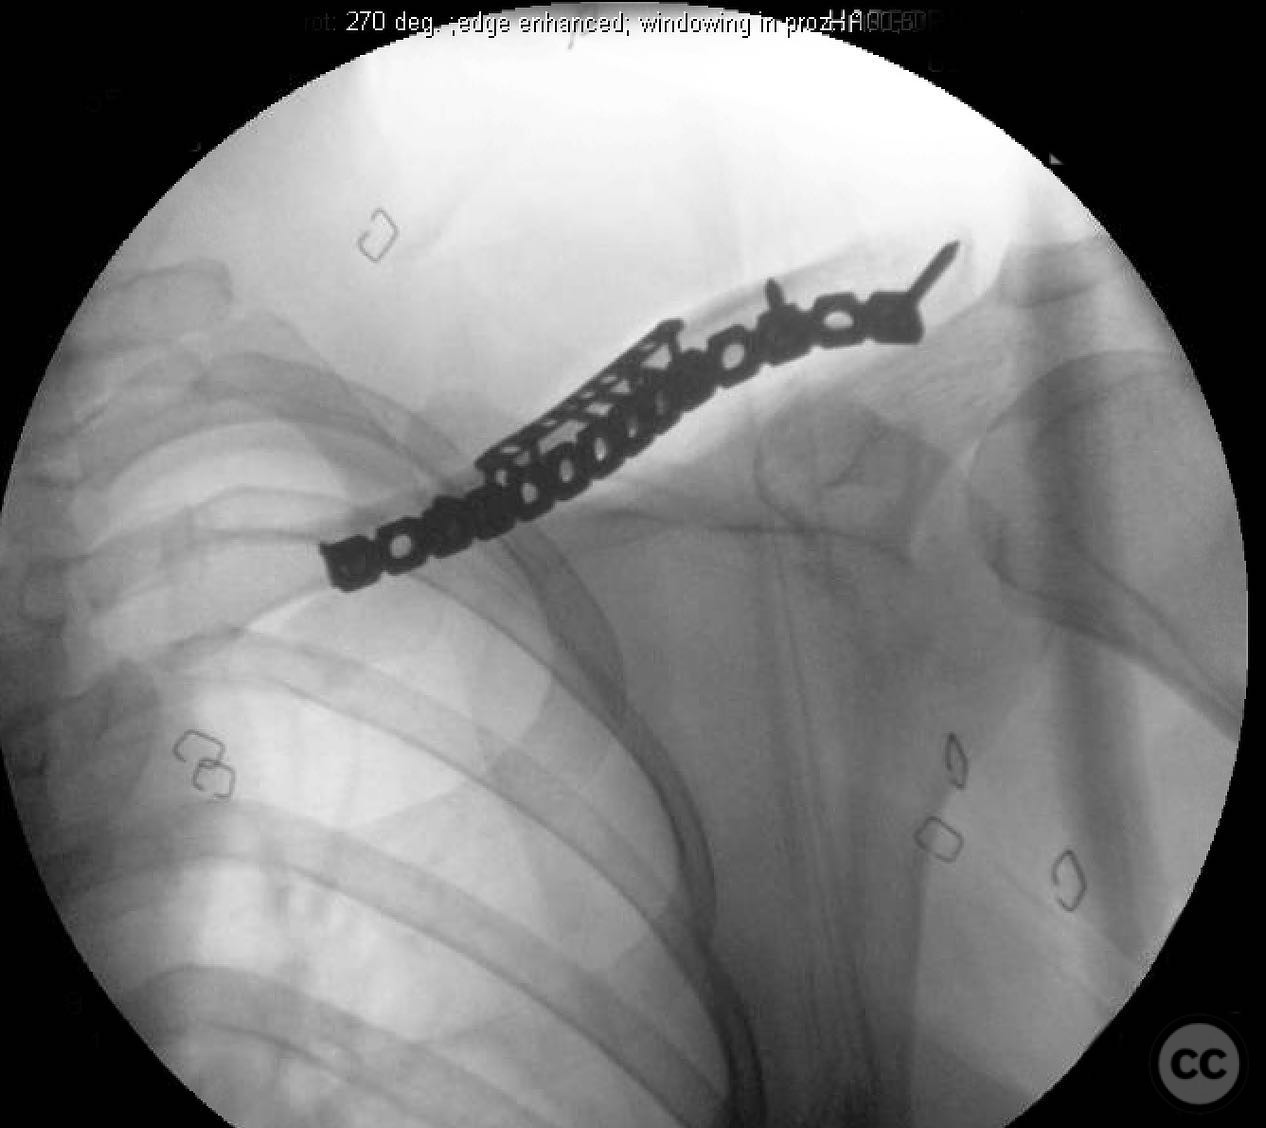

Planning remarks:  The preoperative plan involved direct exposure of the fracture site with anatomic clamp reduction. Interfragmentary compression was planned using lag screws for the butterfly fragments, followed by application of a reconstruction plate on the anterior inferior aspect of the clavicle for neutralization.

During the procedure, anatomic reduction of the butterfly fragments was achieved using 2.4mm lag screws for interfragmentary compression. The main segment reduction proved challenging due to instability; hence, a 2.4mm "clamp replacement plate" was temporarily used to maintain reduction. A reconstruction plate was contoured and applied to the anterior inferior clavicle, providing a neutralization construct. Absolute stability was achieved, anticipating primary bone healing.

Orthopaedic implants used:   2.4mm lag screws, 2.4mm clamp replacement plate, reconstruction plate.